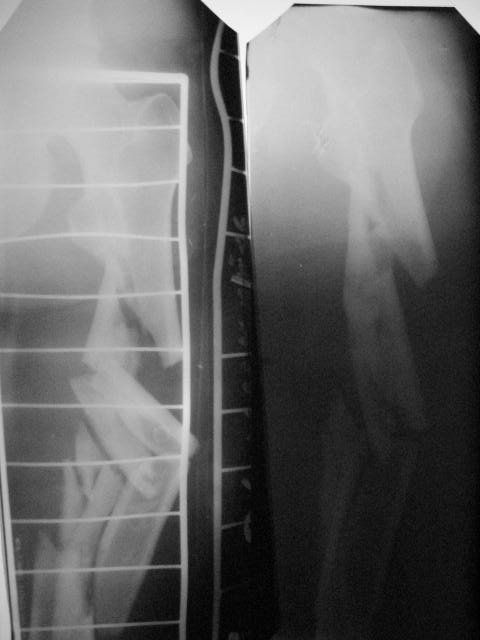

Открытый (2 В Каплан) многооскольчатый перелом левого бедра. Перелом межмыщелкового возвышения большеберцовой кости без смещения слева. Открытый (1 А Каплан) перелом с/3 -н/3 костей правой голени, перелом пяточной кости справа.На седьмые сутки выполнены операции:1. ЗИМО (статически, Chm-CHARFIX) левого бедра. 2. Остеосинтез стержневым аппаратом костей правой голени и пяточной кости. См. r-gr.На сегодня аппарат демонтирован, больной ходит с ограниченной нагрузкой.Смущает стояние отломков в верхней трети бедра (как то не задумались при планировании операции о реконструктивном или гамме штифте ) хватит ли этих двух винтов для стабильности?С Уважением Владимир Бахарев.

Длина проксимального отломка тут достаточна для использования любого диафизарного гвоздя, так что в этом отношении как раз все в порядке. Запас прочности, однако, тут для ранней полной нагрузки недостаточен, и даже с реконструкционным было бы немногим больше - дистальные винты те же 4,5 мм, а они у гвоздей ChM довольно хлипкие. Так что с нагрузкой тут лучше не спешить до уверенных признаков пластики на снимках.

Видна заметная наружная ротация центрального отломка. Если это не случайно сделали снимок, не выведя колено в нейтральное положение, то это типичное смещение, если делать синтез на тракционном столе с тазовой подставкой и промежностным упором. Стоило бы сделать снимок обоих тазобедренных суставов при одинаково уложенных коленных. Для этой же цели можно сделать и снимок в сгибании 90 градусов коленых и тазобедренных суставов, будет прямо видно

антеверсию шеек. Спасибо за презентацию непростого пациента.